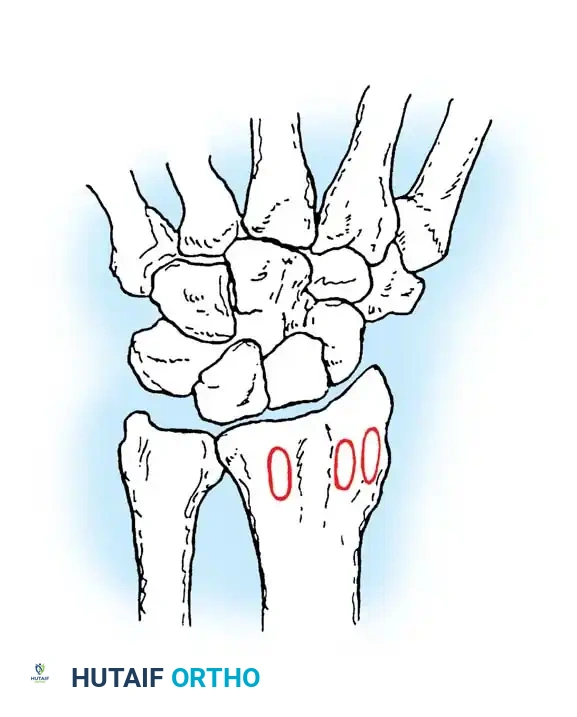

Fig. 54-52 A-F, Schatzker classification of olecranon fractures. (From Browner BD, Jupiter JB, Levine AM, et al, eds: Skeletal trauma, Philadelphia, Saunders, 1992.)

The Schatzker classification includes:

* Transverse: Typically avulsion injuries amenable to tension band wiring.

* Transverse-Impacted: Requires elevation of the impacted articular segment and bone grafting before fixation.

* Oblique: May require lag screw fixation in addition to a neutralization plate or tension band.

* Comminuted: High-energy injuries often requiring plate osteosynthesis to prevent shortening of the greater sigmoid notch.

* Oblique-Distal: Fractures extending distal to the coronoid process, compromising elbow stability.

* Fracture-Dislocation: Complex injuries requiring rigid plate fixation to restore the stabilizing buttress of the proximal ulna.